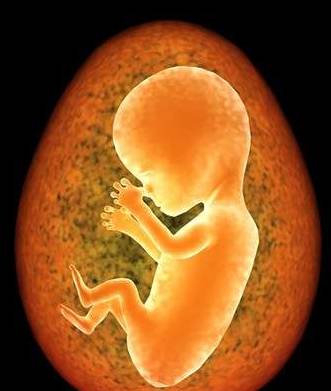

怀孕本身就是一件奇妙而不可思议的事情。

但是孕期还有可能会遇到更多匪夷所思的事,比如以下: